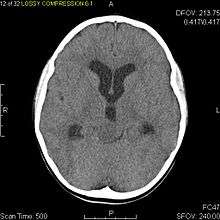

Pilocytic astrocytomas are often cystic, and, if solid, tend to be well-circumscribed. It is characteristically easily seen on CT scans and MRI.

Usually—depending on the interview of the patient and after a clinical exam which includes a neurological exam, and an ophthalmological exam—a CT scan and or MRI scan will be performed. A special dye may be injected into a vein before these scans to provide contrast and make tumors easier to identify. The neoplasm will be clearly visible.